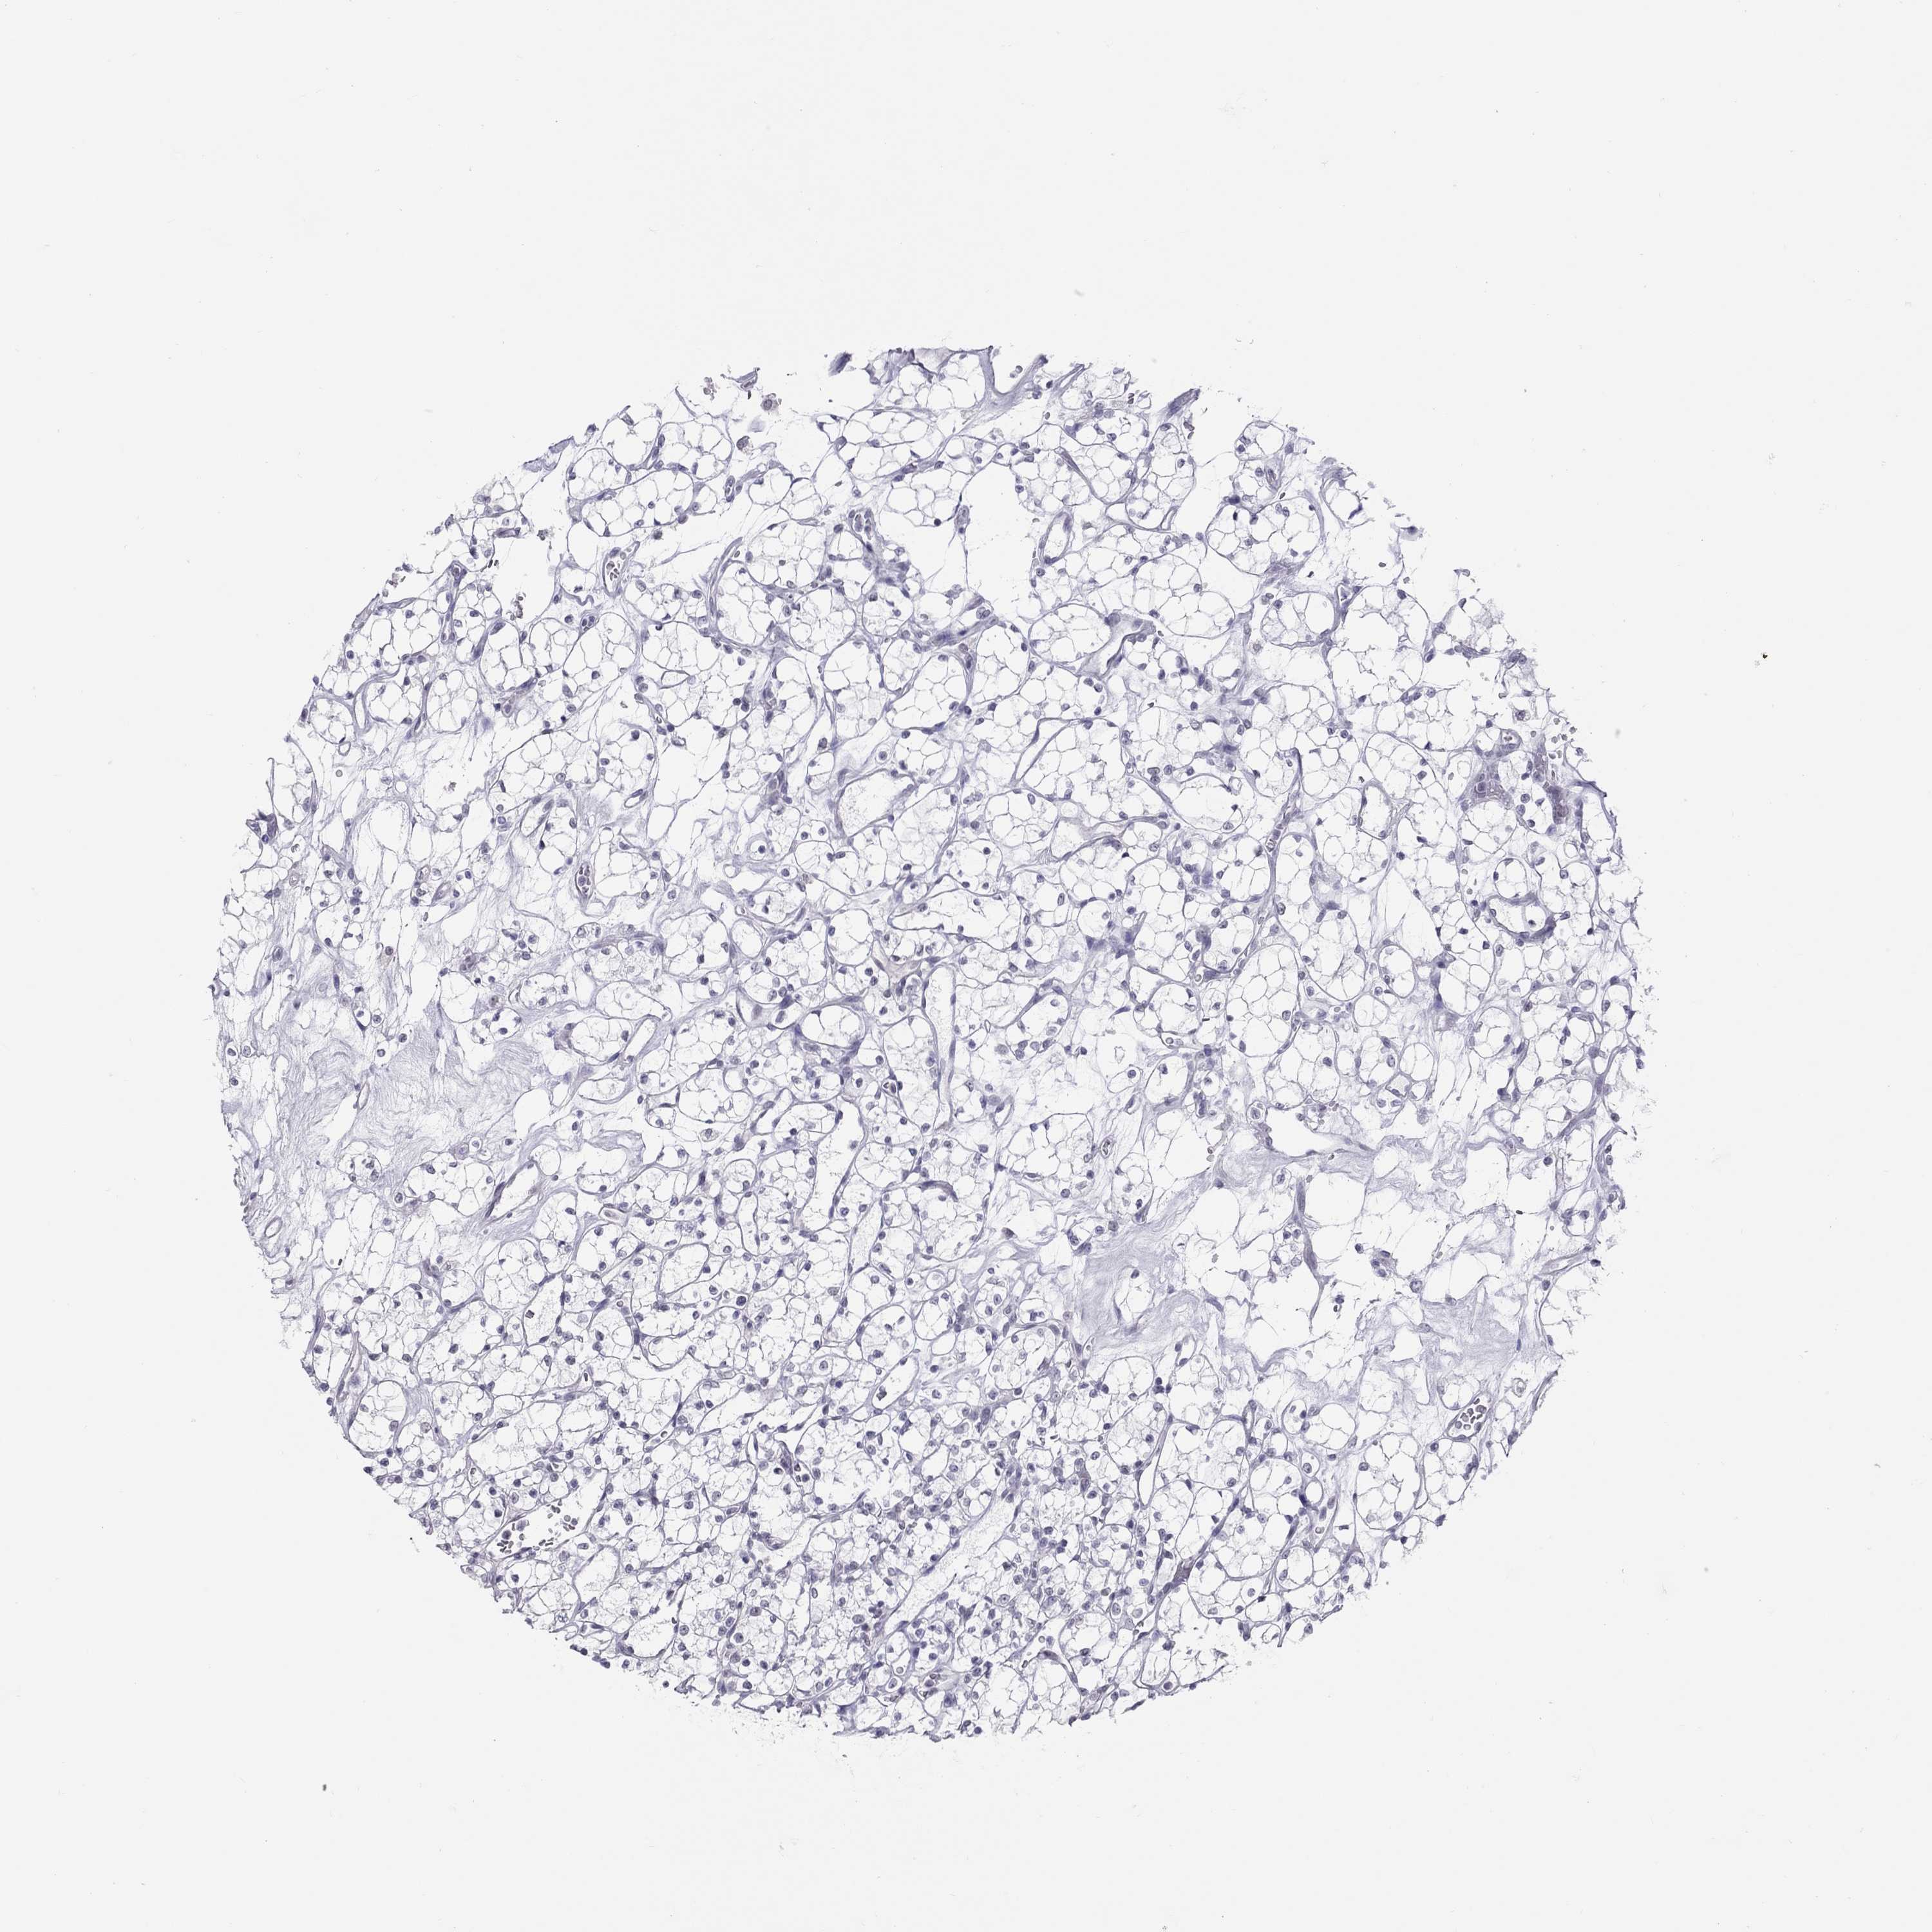

KIDNEY RENAL PAPILLARY CELL CARCINOMA (TCGA) - Interactive survival scatter ploti

The Survival Scatter plot shows the clinical status (i.e. dead or alive) for all individuals in the patient cohort, based on the same data that underlies the corresponding Kaplan-Meier plots. Patients that are alive at last time for follow-up are shown in blue and patients who have died during the study are shown in red.

The x-axis shows the expression levels (FPKM) of the investigated gene in the tumor tissue at the time of diagnosis. The y-axis shows the follow-up time after diagnosis (years). Both axes are complimented with kernel density curves demonstrating the data density over the axes. The top density plot shows the expression levels (FPKM) distribution among dead (red) and alive patients (blue). The right density plot shows the data density of the survived years of dead patients with high and low expression levels respectively, stratified using the cutoff indicated by the vertical dashed line through the Survival Scatter plot. This cutoff is automatically defined based on the FPKM cutoff that minimizes the p-score. The cutoff can be changed by dragging the vertical line or by entering a cutoff value in the square labeled "Current cut-off".

Under the Survival Scatter plot the p-score landscape (black curve; left axis) is shown together with dead median separation (red curve; right axis). Dead median separation is the difference in median mRNA expression between patients who have died with high and low expression, respectively. It is calculated as follows: median FPKM expression of dead patients with high expression - median FPKM expression of dead patients with low expression. This is intended to aid the user in visually exploring custom cutoffs and the associated p-scores and dead median separation.

Individual patient data is displayed and can be filtered by clicking on one or more of the category buttons on the top of the page. Categories describing expression level and patient information include: high, low, alive, dead, female, male and tumor stages. The scale of the x-axis can be toggled between linear and log-scale by clicking on the "x log" button. Mouse-over function shows TCGA ID, patient information and mRNA expression (FPKM) for each patient.

& Survival analysisi

Kaplan-Meier plots summarize results from analysis of correlation between mRNA expression level and patient survival. Patients were divided based on level of expression into one of the two groups "low" (under cut off) or "high" (over cut off). X-axis shows time for survival (years) and y-axis shows the probability of survival, where 1.0 corresponds to 100 percent.

JHY is not prognostic in Kidney Renal Papillary Cell Carcinoma (TCGA)

Best expression cut offi

Based on the FPKM value of each gene, patients were classified into two groups and association between prognosis (survival) and gene expression (FPKM) was examined. The best expression cut-off refers the FPKM value that yields maximal difference with regard to survival between the two groups at the lowest log-rank P-value. Best expression cut-off was selected based on survival analysis .

When clicking on this number, the vertical dashed line indicating cut-off, the interactive survival plot, and the Kaplan-Meier curve will be adjusted to show results based on the best expression cut-off.

: 1.78

Median expressioni